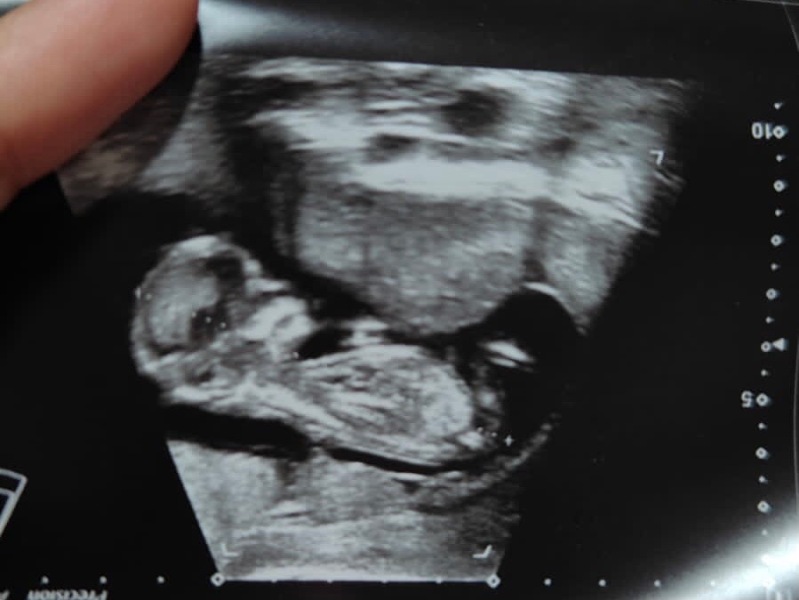

Are the two prominent bones we see a nub? Seems a bit too low, but the shape is so similar to a nub. Any guesses? Thank you :)

Is this a nub?